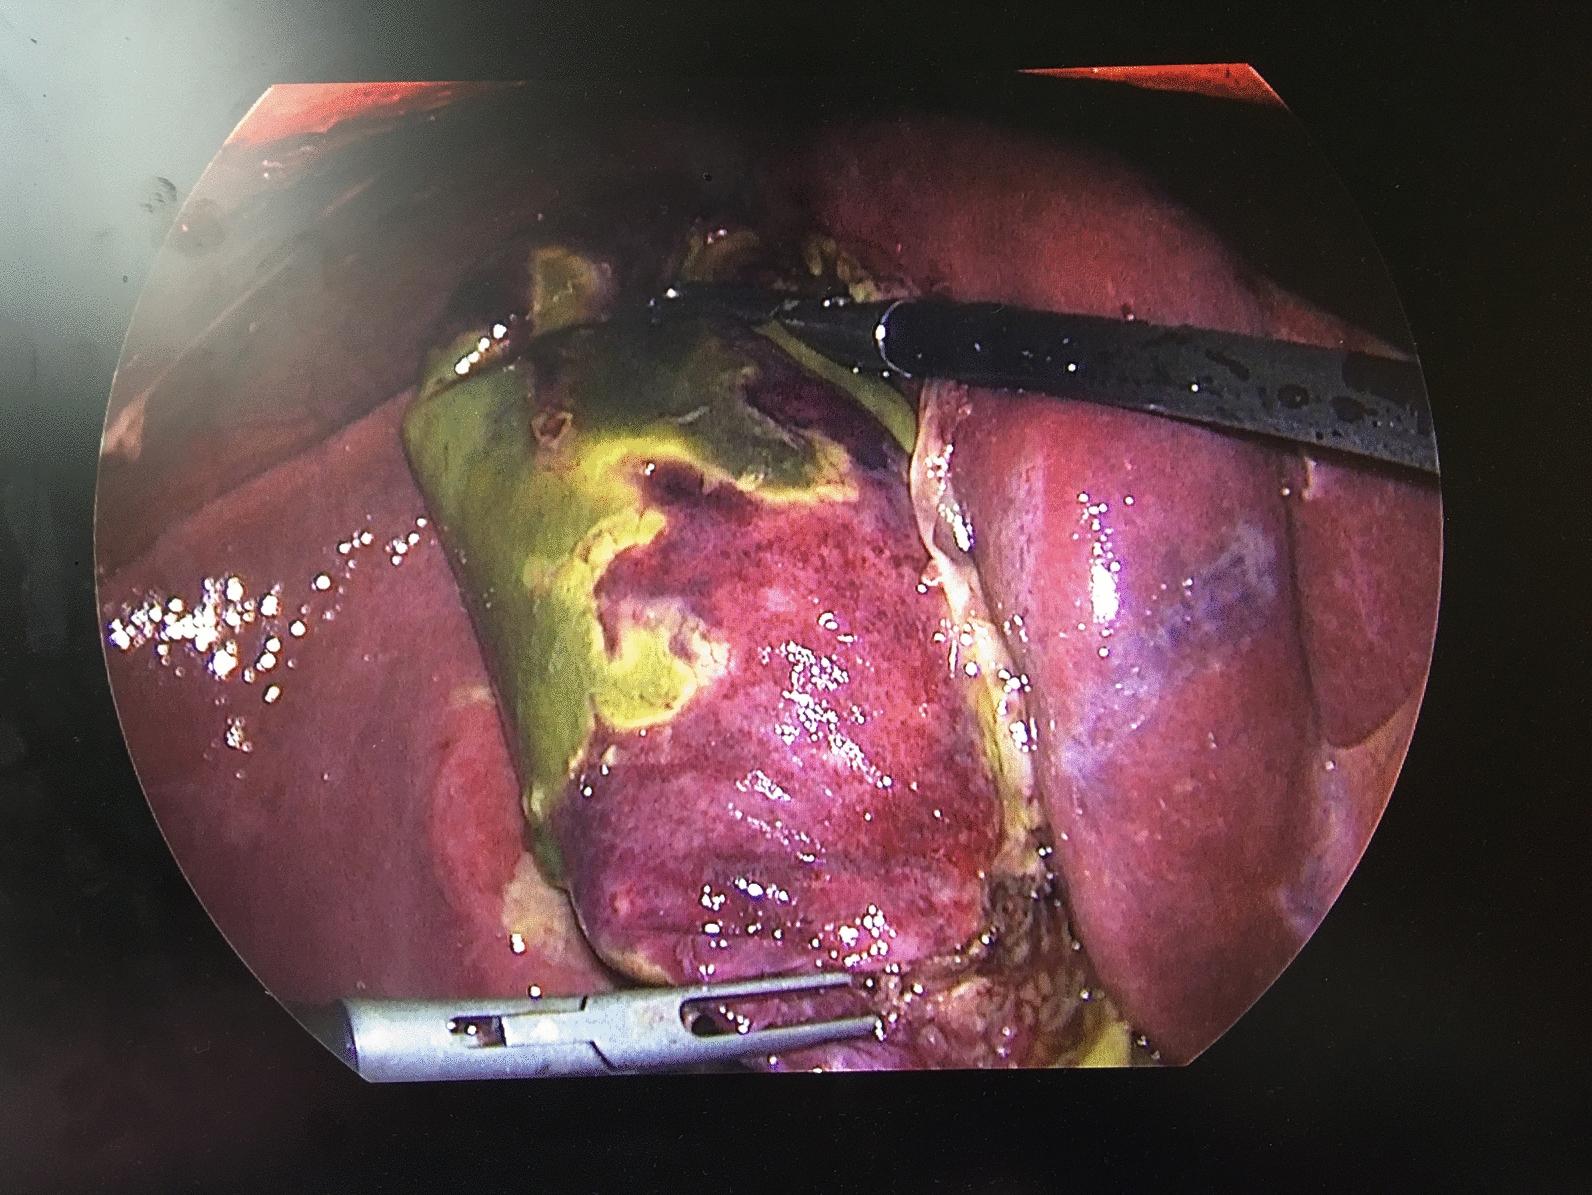

The significant independent factors that predicted death in the logistic regression model with were COVID-19 infection (p < 0.001), postoperative complications (p < 0.001), and type (open/laparoscopic) of surgical intervention (p = 0.003). The odds of death increased 5 times with the COVID-19 infection, 6 times in the presence of complications, and it was reduced by 86% with adequate source control. Survivors predominantly underwent urgent laparoscopic cholecystectomy (52.3% vs. 23.4%).

COVID-19 was an independent risk factor for death in patients with acute cholecystitis. Early laparoscopic cholecystectomy has emerged as the cornerstone of treatment for hemodynamically stable patients.

逻辑回归模型中预测死亡的重要独立因素为COVID-19感染(p < 0.001)、术后并发症(p < 0.001)和手术干预类型(开放/腹腔镜)(p = 0.003)。COVID-19感染使死亡几率增加5倍,出现并发症时增加6倍,而通过充分的源头控制可降低86%。存活者主要接受了急诊腹腔镜胆囊切除术(52.3%对23.4%)。

COVID-19是急性胆囊炎患者死亡的独立危险因素。早期腹腔镜胆囊切除术已成为血流动力学稳定患者治疗的基石。